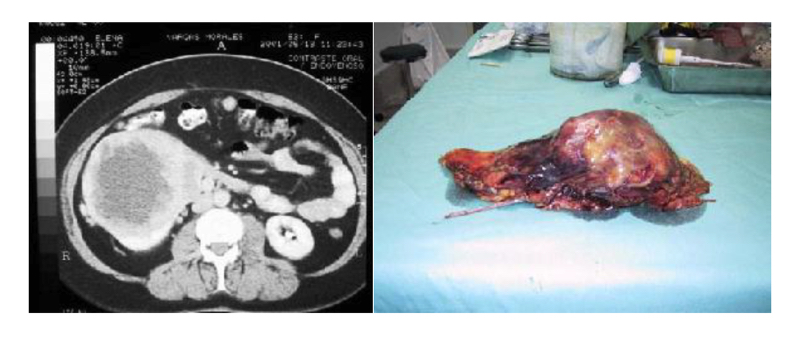

Nefrectomía radical en casos complejos

En relación al tamaño del tumor renal para la vía de abordaje, se ha demostrado que masas renales de > de 10 cm de diámetro, se pueden operar por vía laparoscópica. Determinamos que si los tumores son clínicamente localizados, el tamaño no fue un impedimento para la cirugía. Otros grupos presentaron experiencias similares y concluyeron que no hay diferencias en los resultados, tanto quirúrgicos como oncológicos (21,22) (Figura 22).

Para el abordaje transperitoneal hacemos una distinción entre el lado derecho e izquierdo. Para el lado izquierdo es necesario movilizar el colon descendente incluyendo el ángulo esplénico para exponer ampliamente la Gerota. En el lado derecho, por el gran espacio que deja la corredera parietocólica, pudiera no ser necesario movilizar el colon ascendente. En este caso escindimos directamente el peritoneo y Gerota como un sólo cuerpo, llegando directamente al riñón (Figura 24).

La dificultad que presenta este acceso directo es que el hilio de diseca desde el seno renal, con un mayor riesgo de provocar una lesión vascular. Para quienes tienen una menor experiencia, es recomendable hacer el camino largo, pero más seguro que es decolar el colon derecho, ubicar el plano entre la Gerota y el músculo psoas lumbar y abordar el hilio tal como fue descrito para la nefrectomía radical.

Una vez expuesta la fascia de Gerota, la escindimos ampliamente de polo a polo provocándole el menor daño posible para que al posicionar nuevamente al riñón en su situación original, la podamos suturar. Como requisito para una nefrectomía parcial laparoscópica se requiere obtener una movilidad del riñón que permita posicionarlo para una resección controlada del tumor y una reparación satisfactoria. Muchas veces es necesario desprender el riñón completamente de su grasa peri renal, dejándolo fijo solo del hilio(26,35).